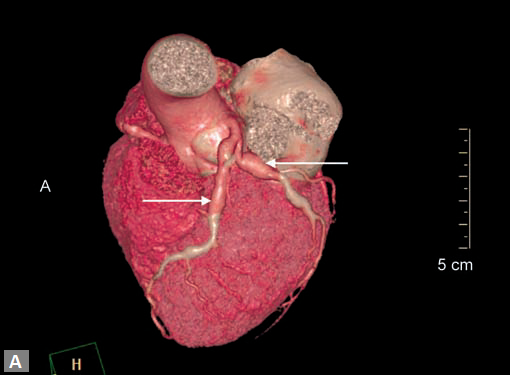

An unusual cause of ischemia is interarterial (so-called

malignant variety) RCA. Demonstration of origin and course

of this vessel is quite easy on CT although the compromise of

lumen is not consistently demonstrated (Figs 7A and B).